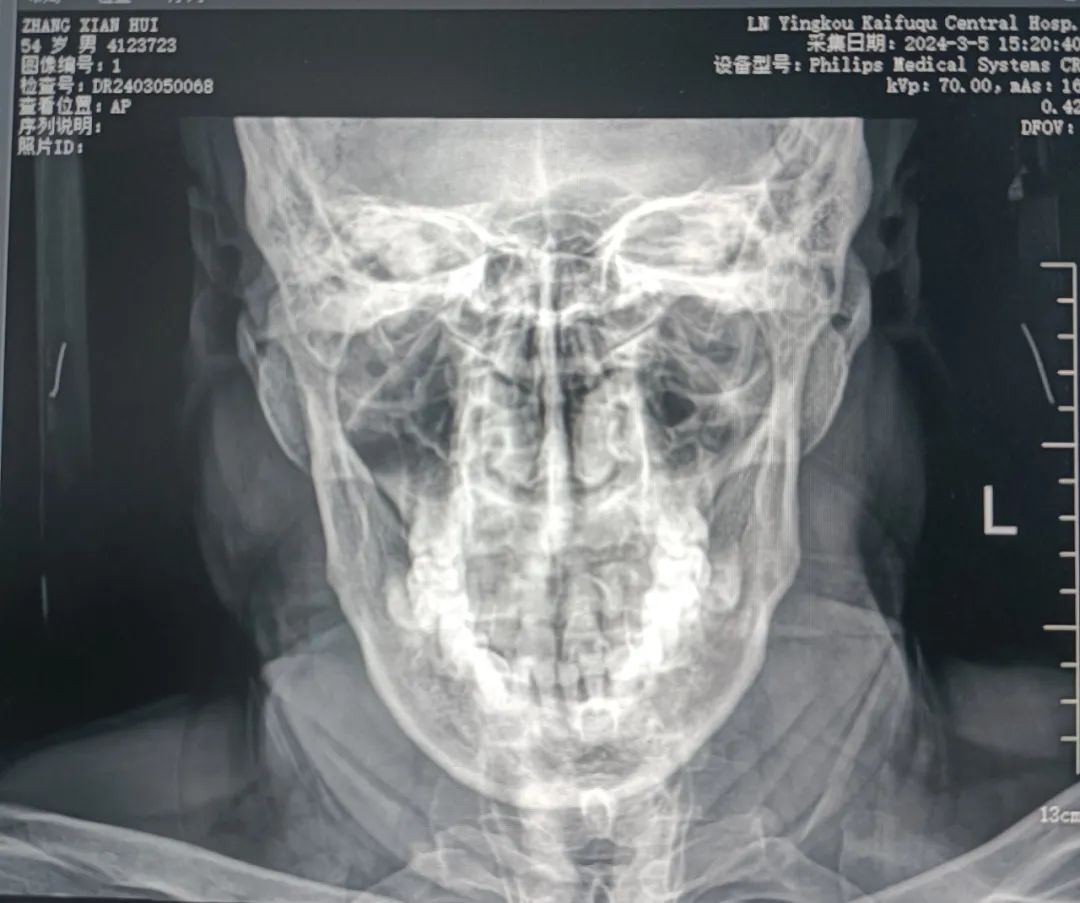

自那以后,张先生总觉得有根鱼刺扎在了喉咙里,咽不下也吐不出。他频繁地前往各大医院就诊,医生们仔细检查后都告知他喉咙里并没有鱼刺。然而,那如鲠在喉的感觉却始终挥之不去。这种不适感让他寝食难安,生活质量严重下降。这三年间,张先生尝试多种治疗办法,可症状没有丝毫改善。直到最近,张先生抱着最后一丝希望来到我院就诊。经过耳鼻喉科赵冬梅主任详细了解病史后,敏锐地察觉到这可能并非单纯的鱼刺问题,凭借丰富的经验,她初步判定患者应为茎突过长引起的咽部异物感,随即为患者安排了喉镜及茎突正侧位片检查。检查结果证实了赵主任的判断,张先生的确患有茎突过长综合征。

茎突正侧位片 显示左侧茎突过长